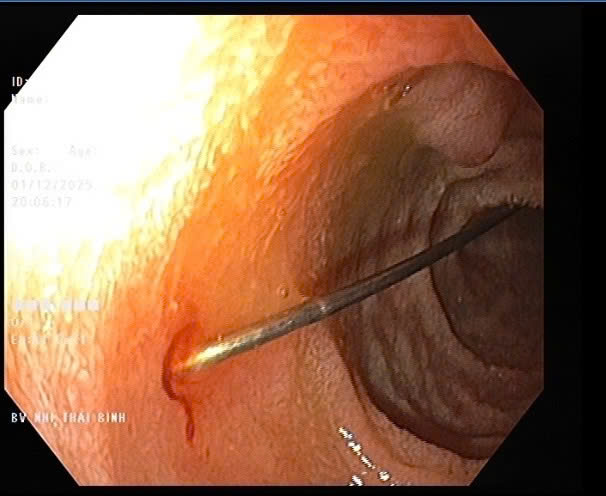

Thủ thuật nội soi được tiến hành lúc 19h12 ngày đội ngũ bác sĩ, điều dưỡng của khoa Tiêu hóa. Hình ảnh nội soi quan sát thấy niêm mạc thực quản và dạ dày của trẻ không viêm loét; tại hành tá tràng D1–D2 phát hiện dị vật kim may dài 4cm, một đầu nhọn cắm vào thành tá tràng, một đầu nhựa tròn hình cúc đang nằm trong lòng ruột. Ê kíp đã sử dụng thòng lọng chuyên dụng tiếp cận đúng vị trí và gắp dị vật ra ngoài an toàn. Thủ thuật diễn ra thuận lợi, không gây trầy xước, không có biến chứng chảy máu sau gắp dị vật